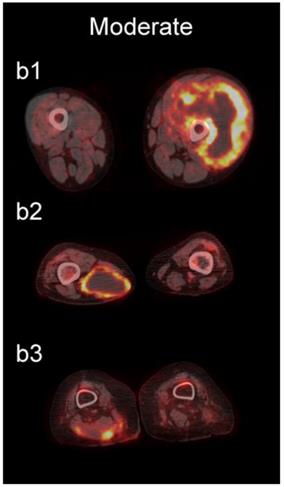

The readers scored the SP of the STSs and BFs on the 4-point avidity scale (Fig. 1). Reader agreement was substantial (κ = 0. 61) and varied among the different SPs, being highest for the thin SP (κ = 0.70) and lowest for the thick SP (κ = 0.46, Table 4). Examples of SPs with 100% reader agreement are shown in Fig. 3.

Figure 3

Examples of lesions with 100% observer agreement on assessment of SP. a Thin SP a1 A 77-year-old woman with a seroma (arrow) 17 days following excisional nodal biopsy (SUVmax = 1.7). a2 A 66-year-old woman with a seroma (arrow) 3 months following excisional nodal biopsy (SUVmax = 2.0). a3 A 21-year-old man with a seroma (arrow) 10 days following excisional nodal biopsy and hydrocele repair (SUVmax = 3.9). b Moderate SP: b1 A 46-year-old man with undifferentiated sarcoma (SUVmax = 19.4). b2 A 38-year-old man with a fungal abscess (SUVmax = 11.6). b3 A 78-year-old woman with recurrent myxoid pleomorphic undifferentiated sarcoma (SUVmax = 5.9). c Thick SP: c1 A 67-year-old man with metastatic undifferentiated sarcoma (SUVmax = 6.3). c2 A 65-year-old man with pleomorphic undifferentiated sarcoma (SUVmax = 30.3). c3 A 45-year-old man with synovial sarcoma (SUVmax = 10.9). d Solid SP: d1 A54-year-old woman with rhabdomyosarcoma (SUVmax = 15.7). d2 A 43-year-old man with pleomorphic undifferentiated sarcoma (SUVmax = 2.7). d3 A 48-year-old woman with myxoid liposarcoma (SUVmax = 2.9).

The SP of STSs was more likely to be assessed as thick or solid by all readers (p<0.0001). Modeling the diagnostic efficacy of a system that classified lesions with a thick or solid SP as an STS yielded an inter-reader averaged sensitivity and specificity of 69% and 98%, respectively.

We also examined the contribution SP to the differentiation of STSs from BFs. SP has not been as extensively investigated as SUV [36-42], and may provide additional information about the biological behavior of soft-tissue lesions on 18F-FDG PET [37]. SP can be assessed qualitatively or quantitatively. Qualitative assessments of heterogeneity, degree of peripheral nodularity, and apparent peripheral thickness of lesions have been used in the past to differentiate benign from malignant lung [38] and peripheral nerve sheath [39] tumors, and to distinguish between high-grade and low-grade STSs [36]. Quantitative algorithms for objective characterization of SP have been used to estimate prognosis in patients with STSs [37, 40, 41] and to assess treatment response in patients with head and neck cancers [42]. Widespread adoption of these quantitative methods has likely been hampered by practical concerns such as time constraints in busy clinical practices. We chose to focus on a qualitative assessment of SP to provide a more readily applied clinical method using an intuitive 4-point scale (Fig. 1) for subjective evaluation of SP (Fig. 3).